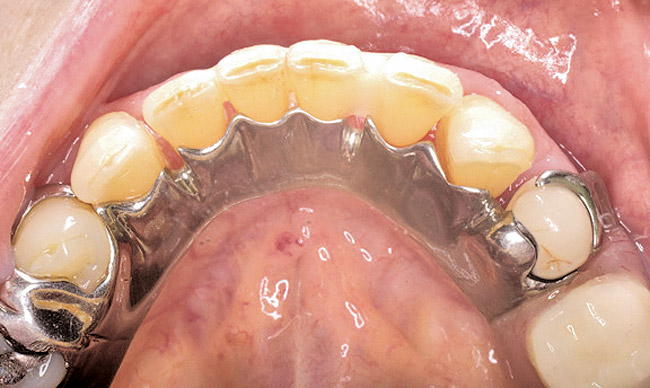

Figure 13  Occlusal view of composite splint.

Figure 13

Then, patient was able to move forward with the prosthesis. Figure 10 shows a periodontal patient who was taking oral bisphosphonates for osteoporosis. The patient had full-mouth scaling and root planing, then was given 2 months to heal and instructed to rinse with chlorhexidine twice daily. After no signs of BRONJ were observed, the patient had full-mouth osseous surgery on her few remaining teeth in the mandible. The surgery was performed all at once and not according to the sextant approach because the patient was on a heart and lung transplant list and was moved up the list while healing from the scaling and root planing. The patient also had extensive bone loss in her anterior mandible (Figure 11).To avoid performing extractions, a simple composite splint was placed between the partial dentures (Figure 12 and Figure 13). The splint reduced the mobility of the teeth and made them less likely to be knocked out during any surgical intubation procedure.